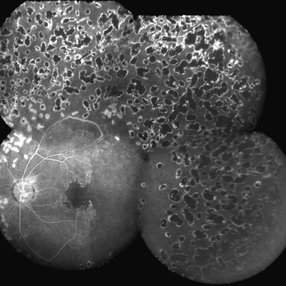

High Risk PDR With Pre Retinal Hemorrhage

A montage of an eye with high risk PDR having pre retinal hemorrhage. Florid NVE are noted in the temporal quadrant. peripheral PRP marks are seen .

Photographer: Ashawini Borde

Imaging device: FF 450 Plus IR

Condition/keywords: hemorrhage, neovascularization of the disc (NVD), nonproliferative diabetic retinopathy, proliferative diabetic retinopathy (PDR)